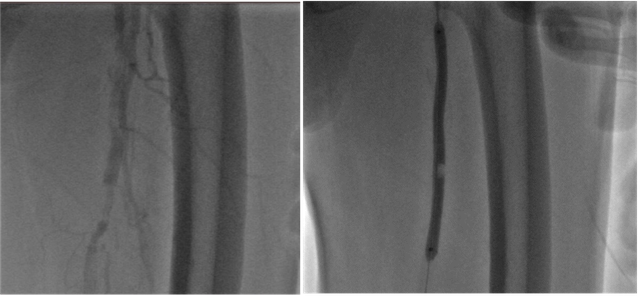

Chụp mạch thấy hẹp - tắc động mạch đùi nông (T)

Chụp mạch sau nong bóng động mạch đùi nông, mạch tái hiện tốt

Sau can thiệp, mạch đùi, mạch khoeo và động mạch chày trước, sau của bệnh nhân nảy rõ, chân ấm, giảm đau chân. Mặc dù tình trạng được cải thiện đáng kể, bệnh nhân vẫn được chỉ định tiếp tục điều trị nội khoa tối ưu và tái khám theo dõi định kỳ.